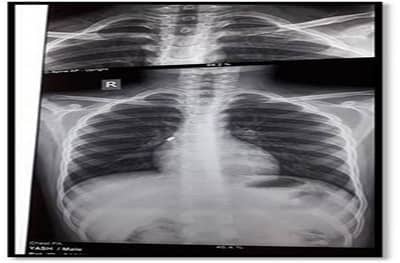

उपचारा दरम्यान डॉक्टरांनी एक्स-रेच्या माध्यमातून घड्याळाचा सेल शोधून काढला. सेल फुफ्फुसामध्ये असल्याचे निदर्शनास आले. यानंतर डॉक्टरांनी शस्त्रक्रिया करत हा सेल बाहेर काढला.